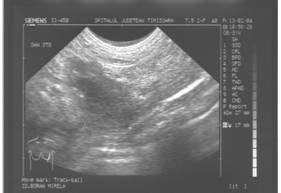

PAPILOM INTRADUCTAL